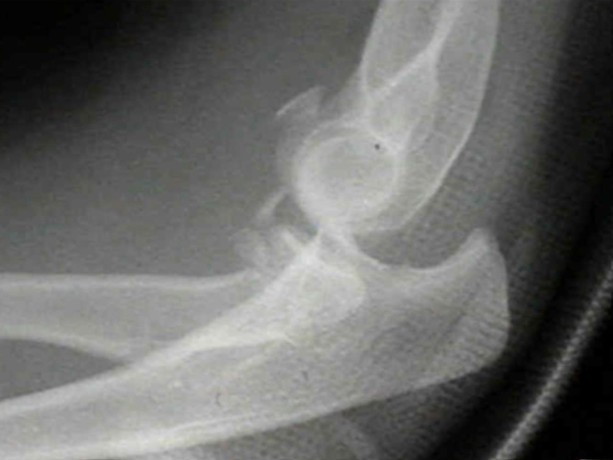

Supracondylar humerus fracture

A 5-year-old girl presents after falling from monkey bars and injuring her right elbow. A lateral X-ray of the elbow …

Elbow injury

You are the ED consultant in a regional centre when a 30-year-old male presents with an isolated left elbow injury …